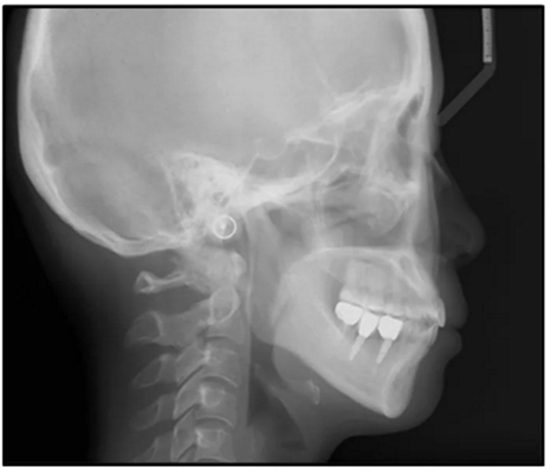

36歲;女性;尋求下頜左后方區(qū)域間隙管理的建議(圖1和圖2),通過(guò)治療獲得了良好的牙頜面效果(圖3和圖4)。她被診斷患有骨性I類(lèi)和代償性牙性II類(lèi)錯(cuò)合畸形,并且上頜左側(cè)尖牙缺失(圖1和2)。大約七年前,由于不可修復(fù)的齲齒,拔除了下頜左側(cè)第一和第二磨牙(圖5)。37相鄰的第三磨牙向近中移動(dòng)并傾斜入間隙,導(dǎo)致無(wú)牙頜間隙減小至約14 mm(圖2和圖5)。臨床和影像學(xué)評(píng)估顯示多發(fā)性齲損和在下頜右側(cè)567處有一不良的固定橋修復(fù)體(圖1和5)。此外,下頜左中切牙缺失,造成下頜中線(xiàn)向左側(cè)偏移約3 mm(圖1和圖2)?;颊咦栽V,她的右上第一前磨牙和左上尖牙在13歲時(shí)由其家庭牙醫(yī)拔除,因?yàn)樗鼈儽蛔枞筋a側(cè)萌出(圖1)。上頜第二磨牙缺失(未知病因),并且相鄰的第三磨牙已經(jīng)轉(zhuǎn)移到第二磨牙間隙中。如補(bǔ)充材料所示,美國(guó)正畸學(xué)差異指數(shù)DI是28分。種植體部位(下頜左側(cè)和右側(cè)第一磨牙)由于復(fù)雜性得到額外4分(補(bǔ)充材料)。

總之,這種復(fù)合錯(cuò)合畸形是一個(gè)很?chē)?yán)重的問(wèn)題,需要進(jìn)行認(rèn)真的多學(xué)科序列治療。治療后X光片(圖6)和重疊頭影測(cè)量圖(圖7)記錄了跨學(xué)科治療結(jié)果。

圖5. 治療前的側(cè)位片(上圖)和全景(下圖)的X光片